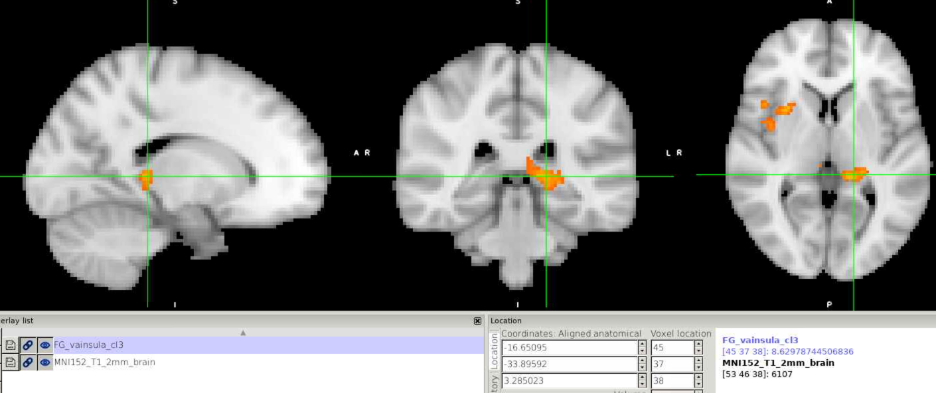

I also looked at the cluster.nii file in FSL eyes, and it seems that the values within that cluster were positive (see attached figure). But this still does not explain why I can't see anything in CONN display.